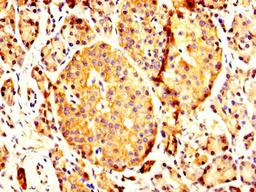

IHC image of CSB-PA017618LA01HU diluted at 1:200 and staining in paraffin-embedded human pancreatic tissue performed on a Leica BondTM system. After dewaxing and hydration, antigen retrieval was mediated by high pressure in a citrate buffer (pH 6.0). Section was blocked with 10% normal goat serum 30min at RT. Then primary antibody (1% BSA) was incubated at 4°C overnight. The primary is detected by a biotinylated secondary antibody and visualized using an HRP conjugated SP system.